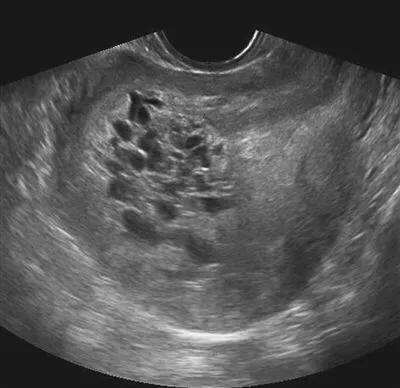

正常情况下,怀孕4-5周超声能看到孕囊,6-7周可以有心管搏动。而葡萄胎的超声,没有这些变化,只有称之为落雪状的影像表现。